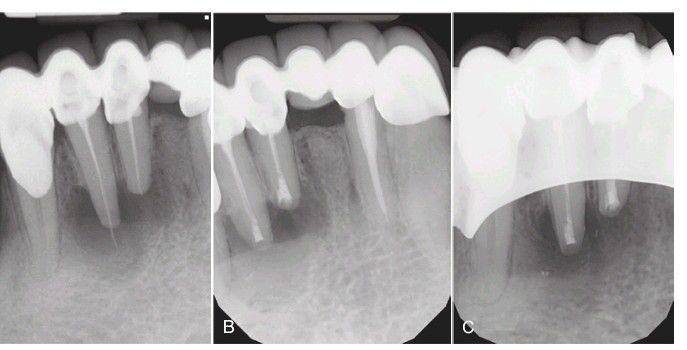

A) Lower incisors with persistent symptoms despite reinstrumentation. The canals are densely filled and a slight overfill is inconsequential as the patient will see the surgeon the same day for apical surgery. (B) At the completion of the apical surgery with placement of a mineral trioxide aggregate retrograde seal. (C) Six months later the bony defect is nearly completely healed without the use of any graft.